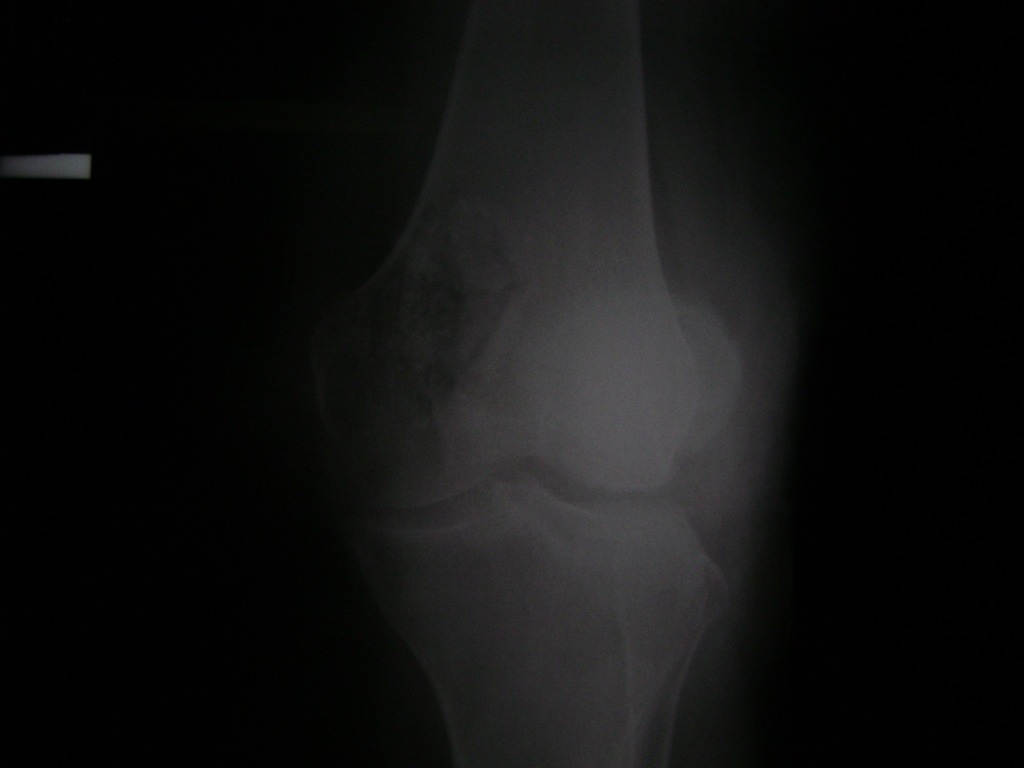

Cirugías de Calcaneo - Rodilla